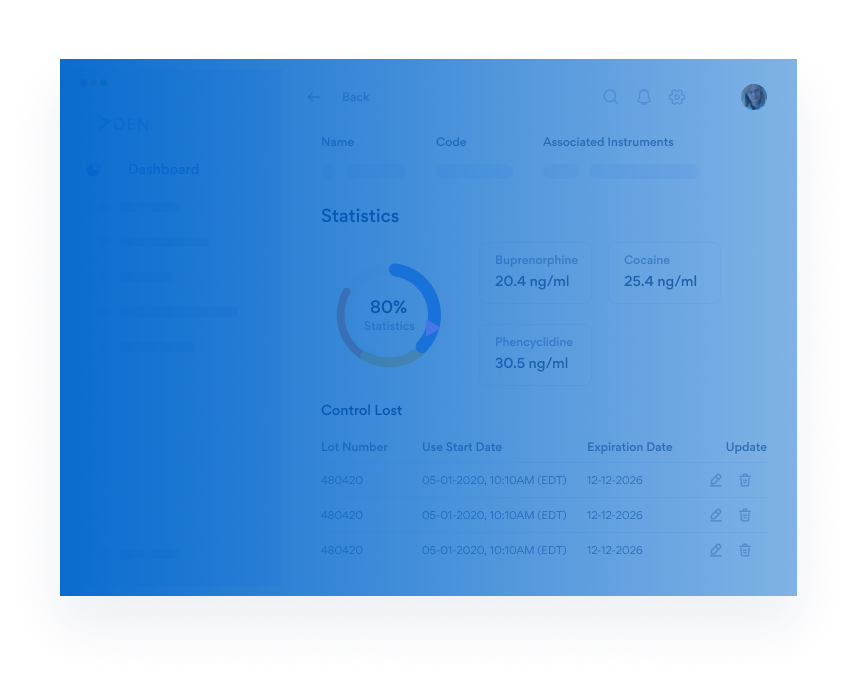

The only constant in healthcare is change. Dendi’s powerful

and user-optimized software platform equips clinical labs

with the tools needed to move forward with confidence.